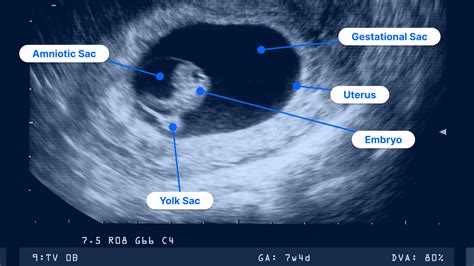

During the ultrasound of 9 weeks, you will likely see a figure that looks less like a "blob" and more like a tiny human. At this stage, the embryo is roughly the size of a green olive or a large grape. Several critical developmental milestones are visible or occurring internally:

Gestational Sac and Yolk Sac: These structures are essential for the early survival of the embryo. The presence of both indicates a healthy, progressing pregnancy. If your scan shows a heartbeat, the statistical risk of miscarriage drops significantly, which often provides a massive sense of relief for expecting parents.